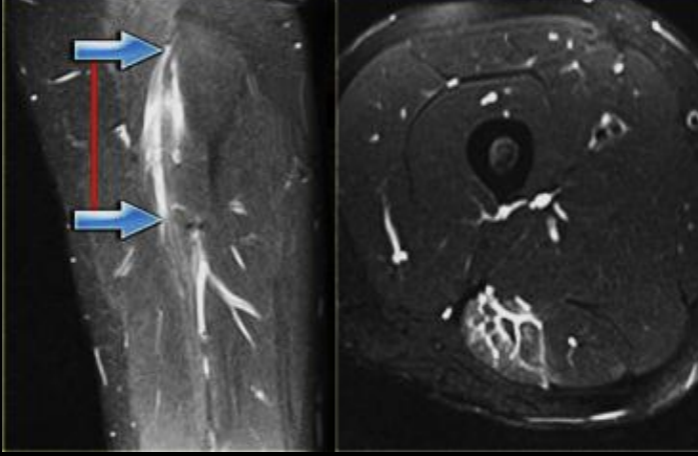

Datos de desgarro muscular en US

Edema y liquido

Disrupción fibrilar

13

A

Desgarro muscular

Grado desgarro en RM

1: hiperseñal pluma de ave

2: disrupcion de fibras

3: disrupciones completa y retracción